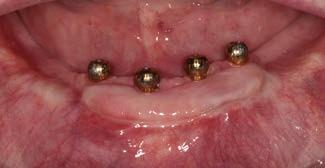

Keratinized tissue around implants

Compared to natural teeth, the soft tissue around dental implants provides less of an anatomical barrier as it does not have inserting fibers attaching to the implant or abutment.2-4 An implant has a transmucosal component (an abutment, neck of the implant, or implant restoration) that protrudes through the overlying mucosa/

gingiva, which heals and adapts around it without an inserting connective tissue attachment such as around teeth. Although some studies showed circular fibers present around the transmucosal part of implants4, it is well-known that the barrier function of the peri-implant tissue is less effective than that of natural teeth. The importance of having sufficient keratinized tissue around dental implants has been emphasized in recent studies.2-5 Mobile alveolar mucosa is not able to provide an adequate seal between the oral environment and the implant body. In patients with inadequate plaque control, this may become even more crucial, as inflammation may distend the mucosa more readily and render the area more uncomfortable to oral hygiene efforts. This in turn may lead to more bone loss around the neck of the implant.2, 4, 6, 7

A reduced width of keratinized tissue around dental implants is associated with increased biofilm accumulation, soft-tissue inflammation, greater patient discomfort, mucosal recession, marginal bone loss and an increased prevalence of peri-implantitis.4, 7 Free gingival autogenous grafts are considered the standard of care for surgical intervention to effectively increase the width of keratinized tissue around dental implants. The presence of a minimum width of at least

2-3mm of keratinized tissue around dental implants should therefore be assessed routinely in patients with implant supported restorations. 7 It should, however, be stressed that the keratinized tissue should have an attached component to protect the coronal bone around the implant to provide an effective seal. In recent studies the importance of adequate thickness of the keratinized tissue has also been emphasized.3

Epithelial palatal transplant (EPT) to increase the width and thickness of keratinized tissue around implants

Grafting of soft tissue can be done at three different time periods: before implant placement (Figs 4a-c), at the same time (Figs 5a-c) or after implant placement (Figs 6a-c). Experienced clinicians may opt to perform an EPT simultaneously with implant placement as this saves multiple surgical procedures and is more cost effective. This is shown in Fig 5 and also in the video link provided. This is a complex procedure which should not be attempted by inexperienced clinicians. Grafting before the implant placement is the more predictable procedure and provides a better implant environment to place the implant.